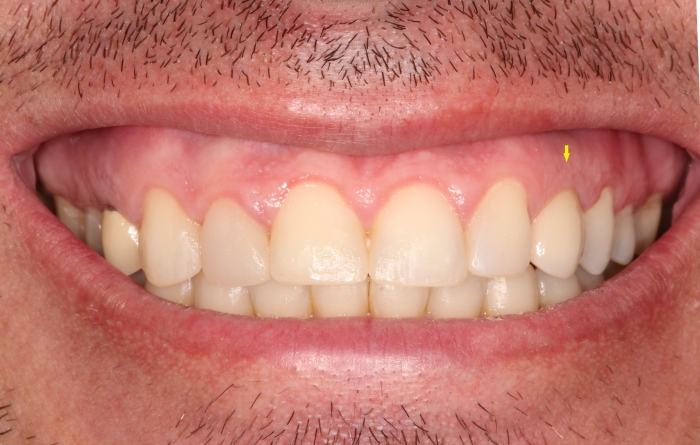

Sorriso final do caso terminado em janeiro de 2013